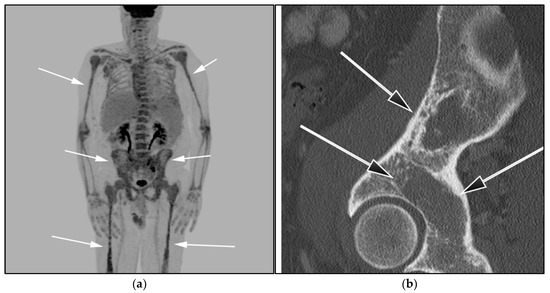

Multimodality imaging, including CT, MRI, and/or 18F-FDG PET/CT, is essential for initial diagnosis, especially in extramedullary disease presentation. Imaging can be helpful in determining optimal biopsy sites, as well as the assessment of response to therapy and monitoring disease progression or transformation. Unlike MM, WM is not associated with definite osseous lytic lesions, a feature that can distinguish WM from MM. WM usually manifests as osteopenia, marrow space widening, and endosteal erosions [52,53] (Figure 11).

Figure 11.

A 85-year-old-male with known diagnosis of lymphoplasmacytic lymphoma (LPL). (a) Maximal intensity projection (MIP) FDG PET/CT image shows extensive hypermetabolic uptake within the spine, pelvis, and proximal upper and distal appendicular skeleton (white arrows). This patient had not received recent marrow stimulating drugs, which can produce imaging findings consistent with marrow infiltration (b). A sagittal CT image shows diffuse osteopenia, marrow space widening, and no discrete focal lesions (black arrows). This is a very important to differentiate from myeloma, which often presents with frankly lytic lesions.

WM patients can also present with splenomegaly with or without focal lesions and lymphadenopathy typically within the axillary, retroperitoneal, and/or inguinal nodal stations (Figure 12). Cranial nerve deficits can be a manifestation of Bing–Neel syndrome, a rare CNS manifestation seen in WM disease [45,48,52,54]. In Bing–Neel syndrome, neurological symptoms can be directly related to infiltration by lymphoplasmacytic cells or indirectly result from the deposition of circulating IgM immunoglobulin on the brain parenchyma, spinal cord, or cranial or peripheral nerves (Figure 13). Additionally, 18F-FDG PET/CT plays an important role in monitoring therapeutic response after treatment initiation, especially with rituximab. WM patients tend to show elevated IgM levels, known as an IgM flare, which may mimic progressive disease. Imaging plays a pivotal role to differentiate between an IgM flare and true progression, thus obviating the need for repeated marrow biopsy [52]. Imaging may also help in excluding the development of myelodysplastic syndromes, acute leukemia, or DLBCL transformation [52].

Figure 12.

Lymphoplasmacytic lymphoma. (a) Axial FDG PET/CT in the same patient as Figure 8 shows hypermetabolic adenopathy within the bilateral iliac chain (white arrows). (b) Sagittal MRI T1-weighted image in the same patient shows a diffuse variegated appearance of the marrow consistent with marrow infiltration as that seen in multiple myeloma but without definite focal lytic lesions. Lymphoplasmacytic lymphoma combines features of both malignant lymphoma and multiple myeloma.